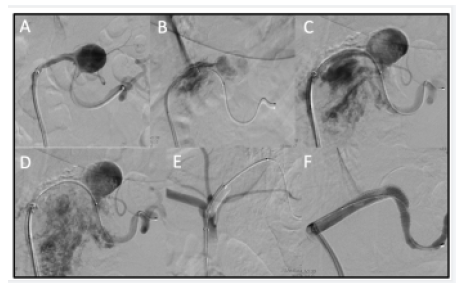

After a multidisciplinary discussion, because of the symptoms and the risk of spontaneous rupture in relation to the remarkable size of the aneurysm, endovascular treatment was recommended. A Cardiatis Multilayer Flow Modulator stent (7X60mm) was initially chosen (Cardiatis, Isnes, Belgium). Under conscious sedation and local anesthesia, the right femoral artery access was obtained and a guidewire was delivered into the distal end of the splenic artery. A 7 Fr guiding multipurpose catheter (Destination, Terumo Medical Corp., Somerset, NJ) was placed over the guidewire. Then, a super-stiff guidewire (Steerable 200 cm) replaced the catheter in order to deliver the Cardiatis stent. Unfortunately, during these maneuvers, the rupture of the SAA occurred. Due to this complication, the treatment strategy was modified. An occluding balloon-catheter was deployed, and, subsequently, two 8 mm Viabahn stent-grafts were successfully placed under digital subtraction angiography roadmap guidance to exclude the aneurysm. Repeated angiography confirmed good location and shape of stent-grafts. Patency of the distal portion of the splenic artery was evidenced and no obvious residual aneurysm was visualized (Figure 2).

Figure 2: Digital subtraction angiography (A-F). During the catheterization, the rupture of the aneurysm occurred (B-D). The treatment strategy changed: an occluding balloon-catheter and two 8 mm Viabahn stent-grafts were deployed under digital subtraction angiography roadmap guidance, to exclude the aneurysm (E,F).